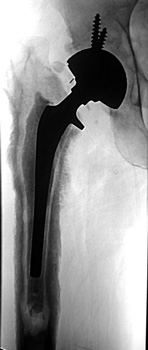

Normal arthrogram

Arthrographic evidence of looseningcontrast enters

abnormally widened interface Gruen zone 1 and 2

Arthrographic evidence of cup looseningcontrast enters

abnormally widened interface Gruen zone II and III